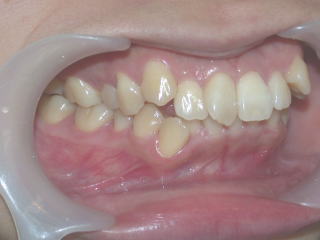

2022年7月25日初診、20代女性の叢生症例 (新潟県長岡市要町 要町歯科 歯科矯正 歯列矯正)

術前術後

2022年7月→2024年5月(2年弱でした。これから保定期間に入ります。)